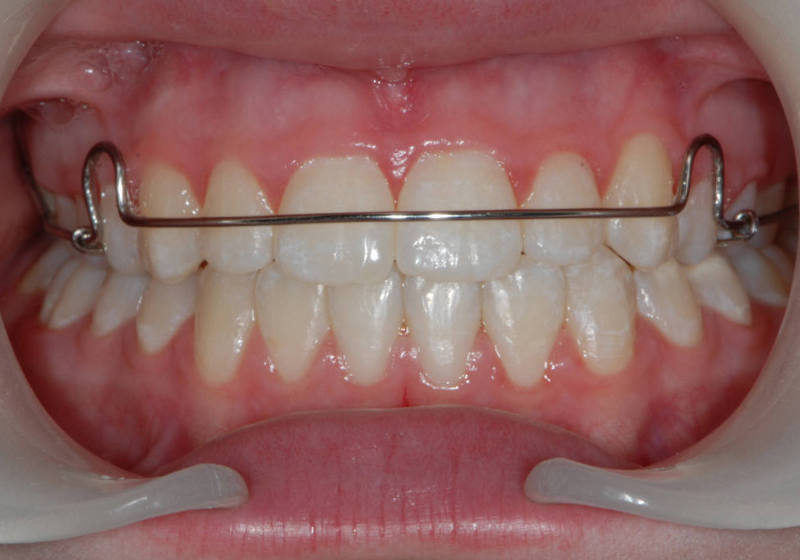

TwistFlex retainer